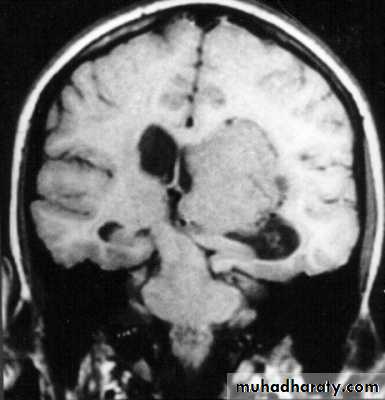

Clinical Picture: patient will present with a picture similar to that of an extradural haematoma, but there is persistent loss of consciousness with no lucid interval.Ct scan will show a concave hyperdence collection because blood follows the subdural space over the convexity of the brain.

Acute Subdural Haematoma are rapidly evolving lesions and early evacuation via craniotomy is mandatory.

Acute Subdural Haematoma